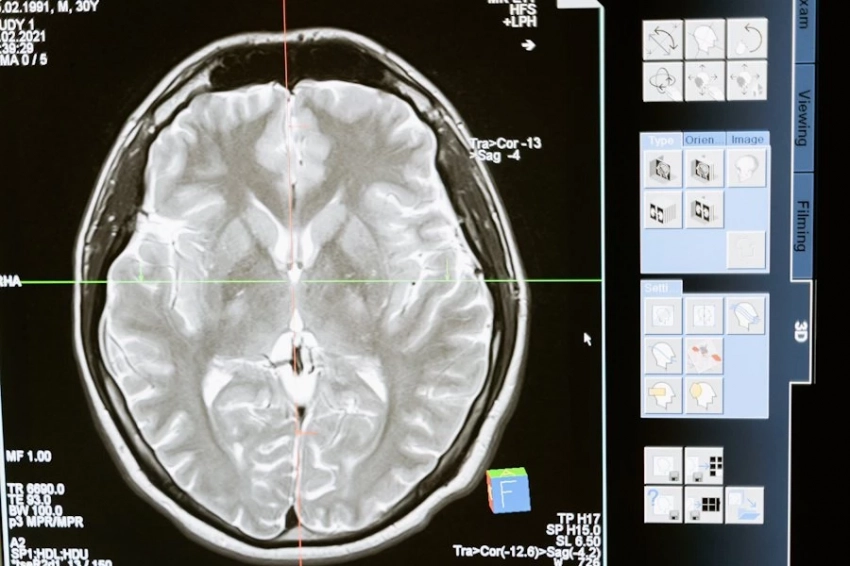

Всего было обследовано 739 когнитивно здоровых участников, 389 из которых были женщинами в возрасте 70 лет. Мозг этих людей был исследован с помощью МРТ, что позволило команде оценить возраст мозга с помощью алгоритма на основе искусственного интеллекта.

В дополнение к МРТ головного мозга были взяты образцы крови для измерения липидов, глюкозы и маркеров воспаления. Кроме того, участники прошли различные когнитивные тесты и были собраны данные о факторах образа жизни (например, физической активности и медицинских заболеваниях).